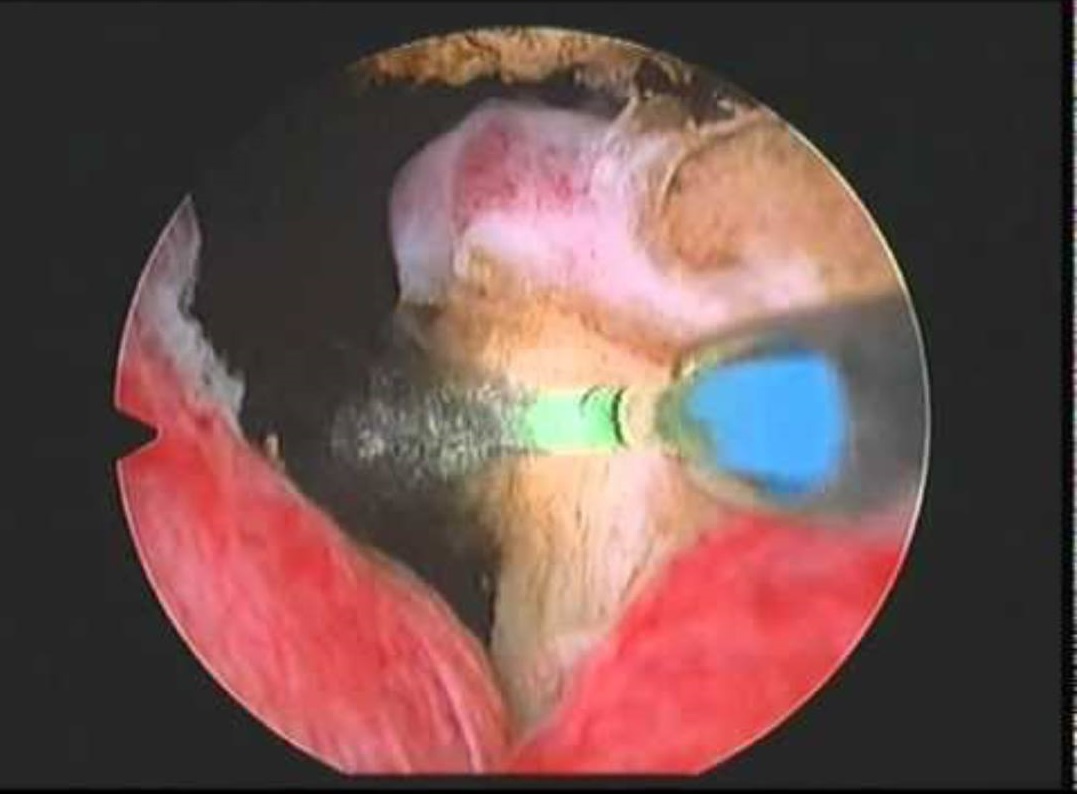

وأكد الدكتور قاسم أن قسم المسالك البولية قد قطع شوطا كبيرا في عمليات المنظار البطني، حيث تم إجراء عدد من العمليات النوعية لاستئصال الكلية أو جزء منها، واستئصال حصوات كبيرة من حوض الكلية، مشيرا إلى إنجاز أخير جرى بواسطة تداخلا جراحيا بالمنظار لسيدة في الثلاثينيات من عمرها، كانت تعاني من تضيق خلقي في مقطع الحالب عند دخوله لحوض الكلية، الأمر الذي تسبب لها بآلام والتهابات وقصور في وظيفة الكلية، فيما جرى استصال كامل للجزء الضيق وإعادة توصيله لحوض الكلية بواسطة المنظار الجراحي، وذلك عن طريق أربعة ثقوب صغيرة في جدار البطن كبديل لتقنية الشق الجراحي التقليدية وتجنبا لمضاعفاتها.